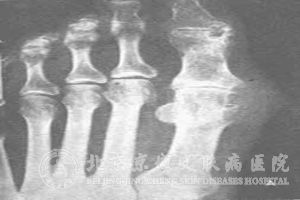

痛风与其他疾病有哪些关系呢?痛风是一种很常见的老年性疾病,很多上了年纪的人较容易被痛风缠上。痛风有一个比较明显的特征就是40以上的男人比较常见,很多人都不了解原因,这时因为男人接触的筵席比较多,摄入过多的含嘌呤物质,就很容易引发痛风。除此之外,痛风还与哪些疾病有密切的联系呢?